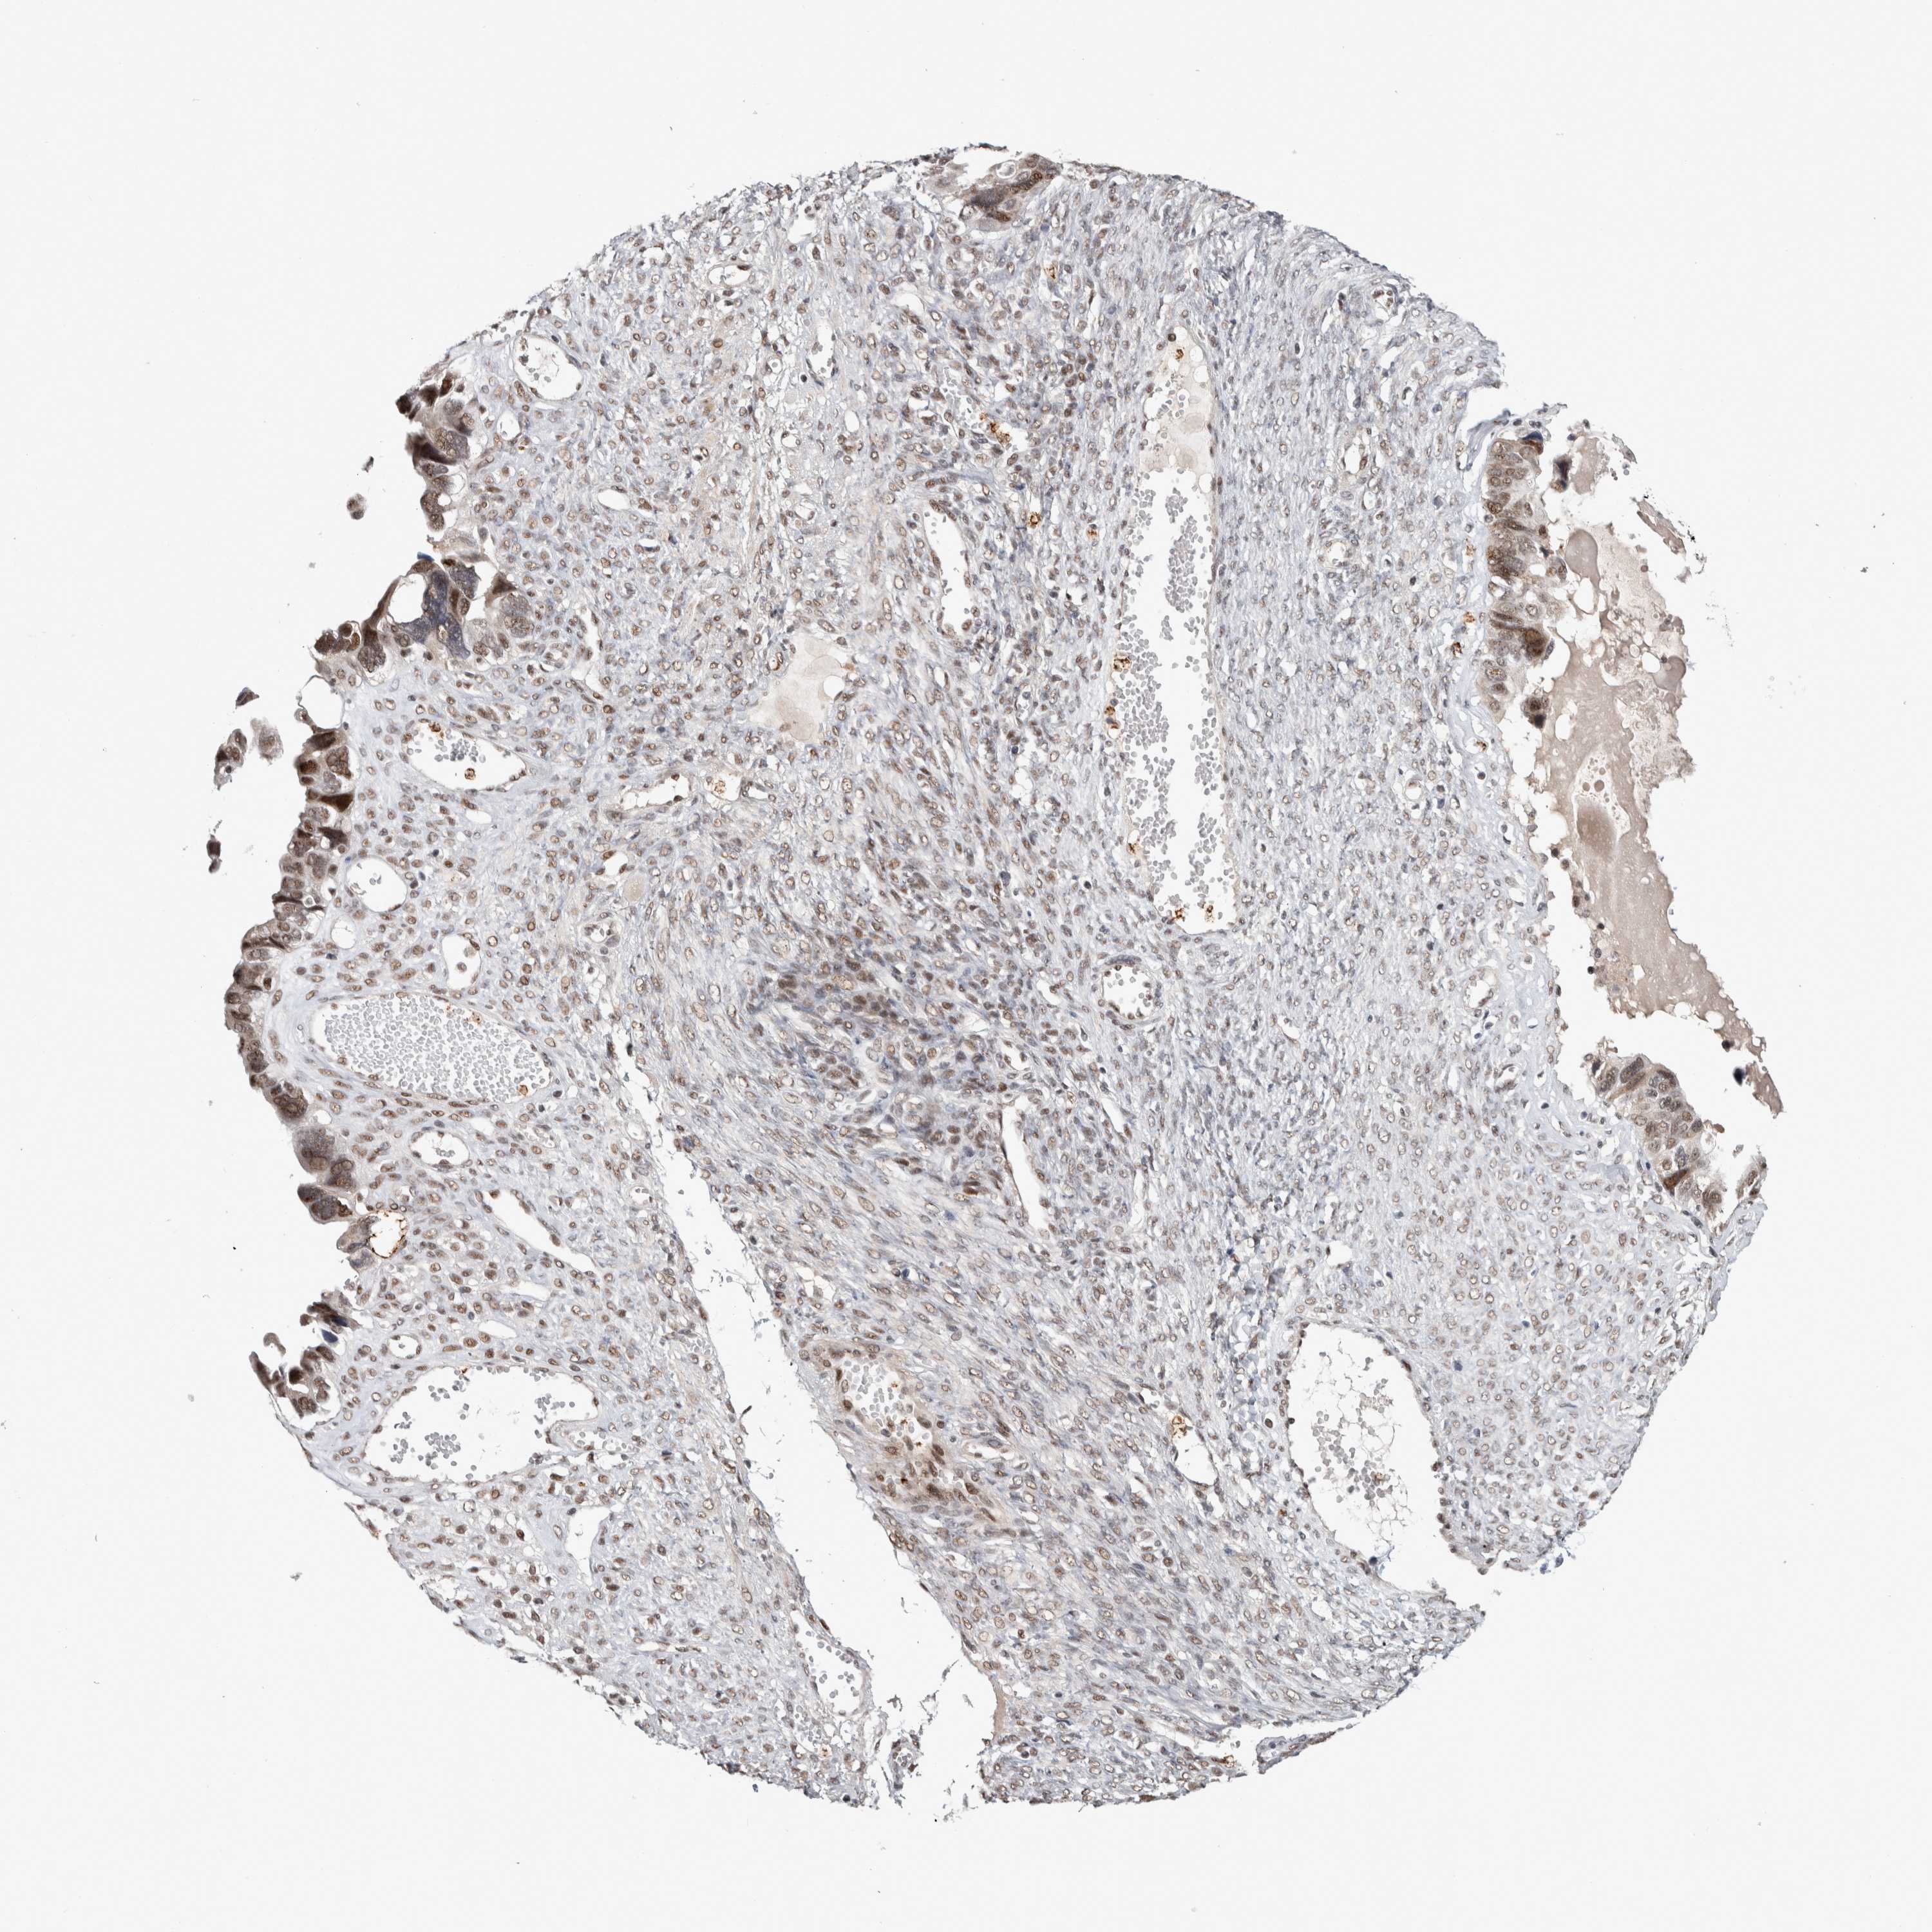

OVARIAN CANCER - Protein expressioni

A mouse-over function shows sample information and annotation data. Click on an image to view it in a full screen mode. Samples can be filtered based on level of antibody staining by selecting one or several of the following categories: high, medium, low and not detected. The assay and annotation is described here.

Note that samples used for immunohistochemistry by the Human Protein Atlas do not correspond to samples in the TCGA dataset.

Antibody stainingi

Antibody staining in the annotated cell types in the current human tissue is reported as not detected, low, medium, or high, based on conventional immunohistochemistry profiling in selected tissues. This score is based on the combination of the staining intensity and fraction of stained cells.

Each image is clickable and will lead to virtual microscopy that enables deeper exploration of all samples and also displays staining intensity scores, fraction scores and subcellular localization as well as patient and tissue information for each sample.

Antibody HPA008435

Antibody HPA024230

Staining

High

Medium

Low

Not detected

Intensity

Strong

Moderate

Weak

Negative

Quantity

>75%

75%-25%

<25%

None

Location

Nuclear

Cytoplasmic/membranous

Cytoplasmic/membranous,nuclear

Cystadenocarcinoma, serous, NOS

Carcinoma, endometroid

Cystadenocarcinoma, mucinous, NOS

Carcinoma, NOS